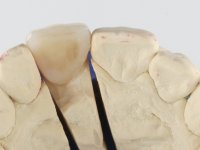

Female patient, 41 years old, non-smoker. It presented tooth 11 with a composite resin restoration, of great extension, very infiltrated and aesthetically poor. In the imaging exam, it was verified that the endodontic treatment was not technically satisfactory, but asymptomatic for almost 20 years. Between teeth 11 and 12 it showed a periodontal pocket certainly related to the non-adapted restoration. Tooth 11 showed a reduced mesiodistal diameter in relation to the symmetrical one. Medium thickness periodontal with satisfactory oral hygiene.

It was proposed to the patient to make a full-coated crown with a ceramic-coated Zr infrastructure that would aesthetically and functionally rehabilitate tooth 11. We decided not to redo the endodontic treatment given the absence of signs and symptoms for more than 20 years. The coronary structure would be previously reinforced with the placement of an intraradicular post and the making of a new restoration in composite resin. Periodontal pocket would be surgically addressed.

The treatment began with the placement of an intraradicular post and the creation of a new composite resin restoration. This procedure was performed with a surgical approach that allowed the remaining margins to be completely exposed, which were shown to be at a very infra-gingival level. Simultaneously, the periodontal pocket was curetted and root scaling and root planning of adjacent teeth were performed. Two months after this first intervention, the making of the crown began. A pre-print on silicone was performed to make a temporary crown with dual-cured composite resin. Gingival retraction was performed using the technique of kaolin paste compressed by the provisional crown. The impression was made using the double-mix technique with double viscosity with quick-setting silicone. In the laboratory, a crown with a ceramic-coated Zr infrastructure was made. The crown slightly overlapped tooth 12, allowing a dimensionally mimicry of the symmetrical tooth. Its fit was confirmed and approved by the patient; it was definitively cemented with resin-reinforced glass ionomer cement.